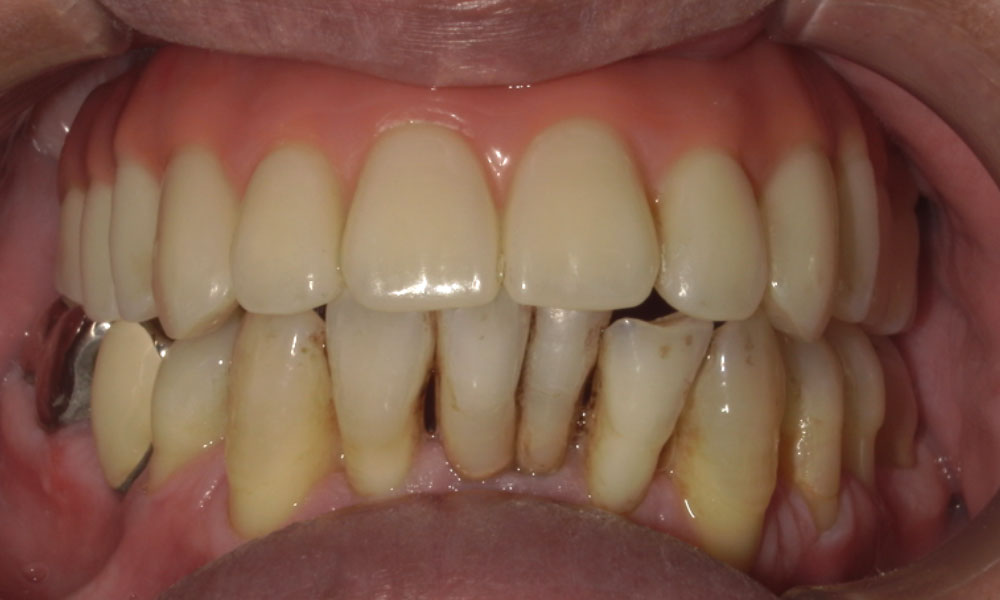

手術後口腔内